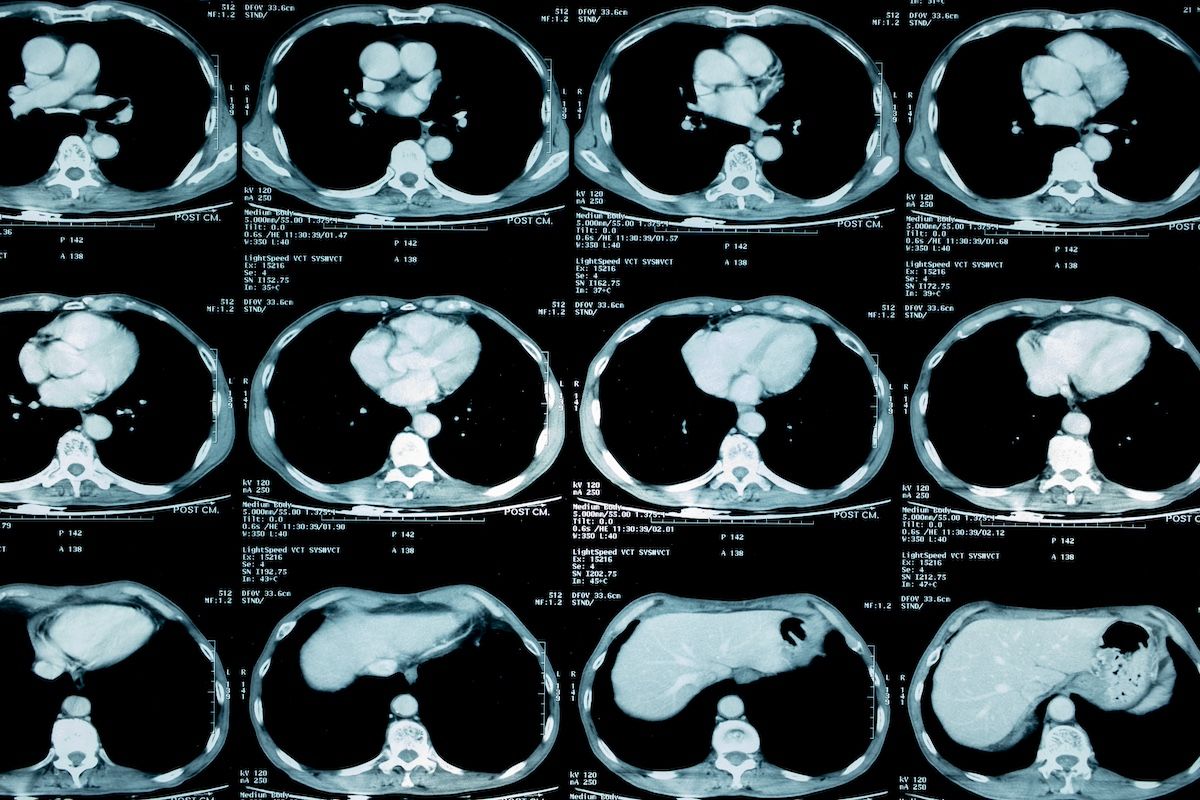

Of this patient population, all underwent TSB between January 2015 and June 2021, had not been diagnosed with lung cancer or extrathoracic metastatic disease, and were identified through their electronic medical records. Those in the malignancy cohort were slightly older (68.3 years vs 65.1 years [P = .09]); female patients made up most of this cohort (55%), while male patients made up most of the nonmalignant resection cohort (85.2%). Most of the overall group was White (71.4% of the malignant cohort and 80% of the nonmalignant cohort) and former smokers (75% and 69.2%, respectively). The investigation began with 80 patients who had a screening low-dose lung CT (LDCT), before being whittled down to 54 after 24 patients were found to have preoperative lung cancer and 2, metastatic disease.

In this analysis, most patients had surgery followed by 4 months of surveillance; 40 patients overall were diagnosed with a malignancy | Image Credit: kae2nata-stock.adobe.com

Three procedures dominated following the LDCT. Most patients (46.3%) proceeded to surgery and followed that with 120 days of surveillance or presurgical bronchoscopy or transthoracic needle aspiration (TTNA), 29.6% had surgery but did surveillance first, and 24% had a nondiagnostic bronchoscopy or TTNA prebiopsy. From these procedures’ findings, the patients were divided into 2 groups. Fourteen patients were diagnosed with benign disease (25.9%; 95% CI, 14.9%-39.7%), and 40 patients were diagnosed with a malignancy (74%).